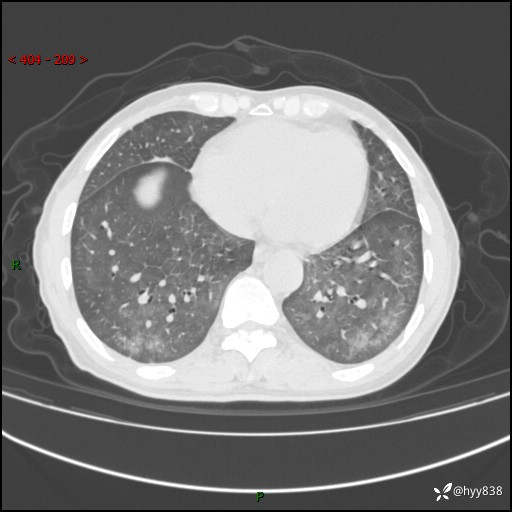

辅助检查:CT

胸部CT平扫

不是讨论肺部结节